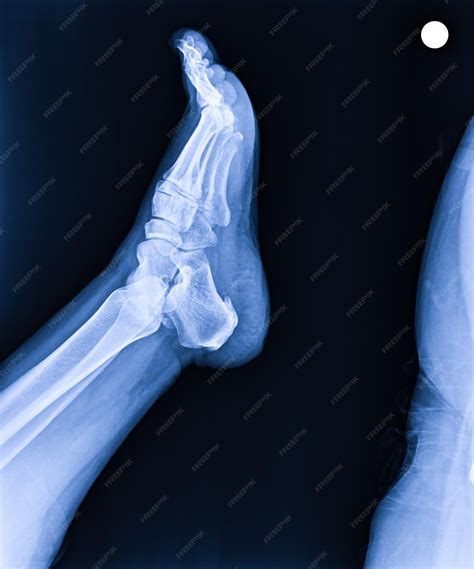

Lateral View Shows the side of the foot, providing a profile view of the bones and joints.

• normal foot x ray series